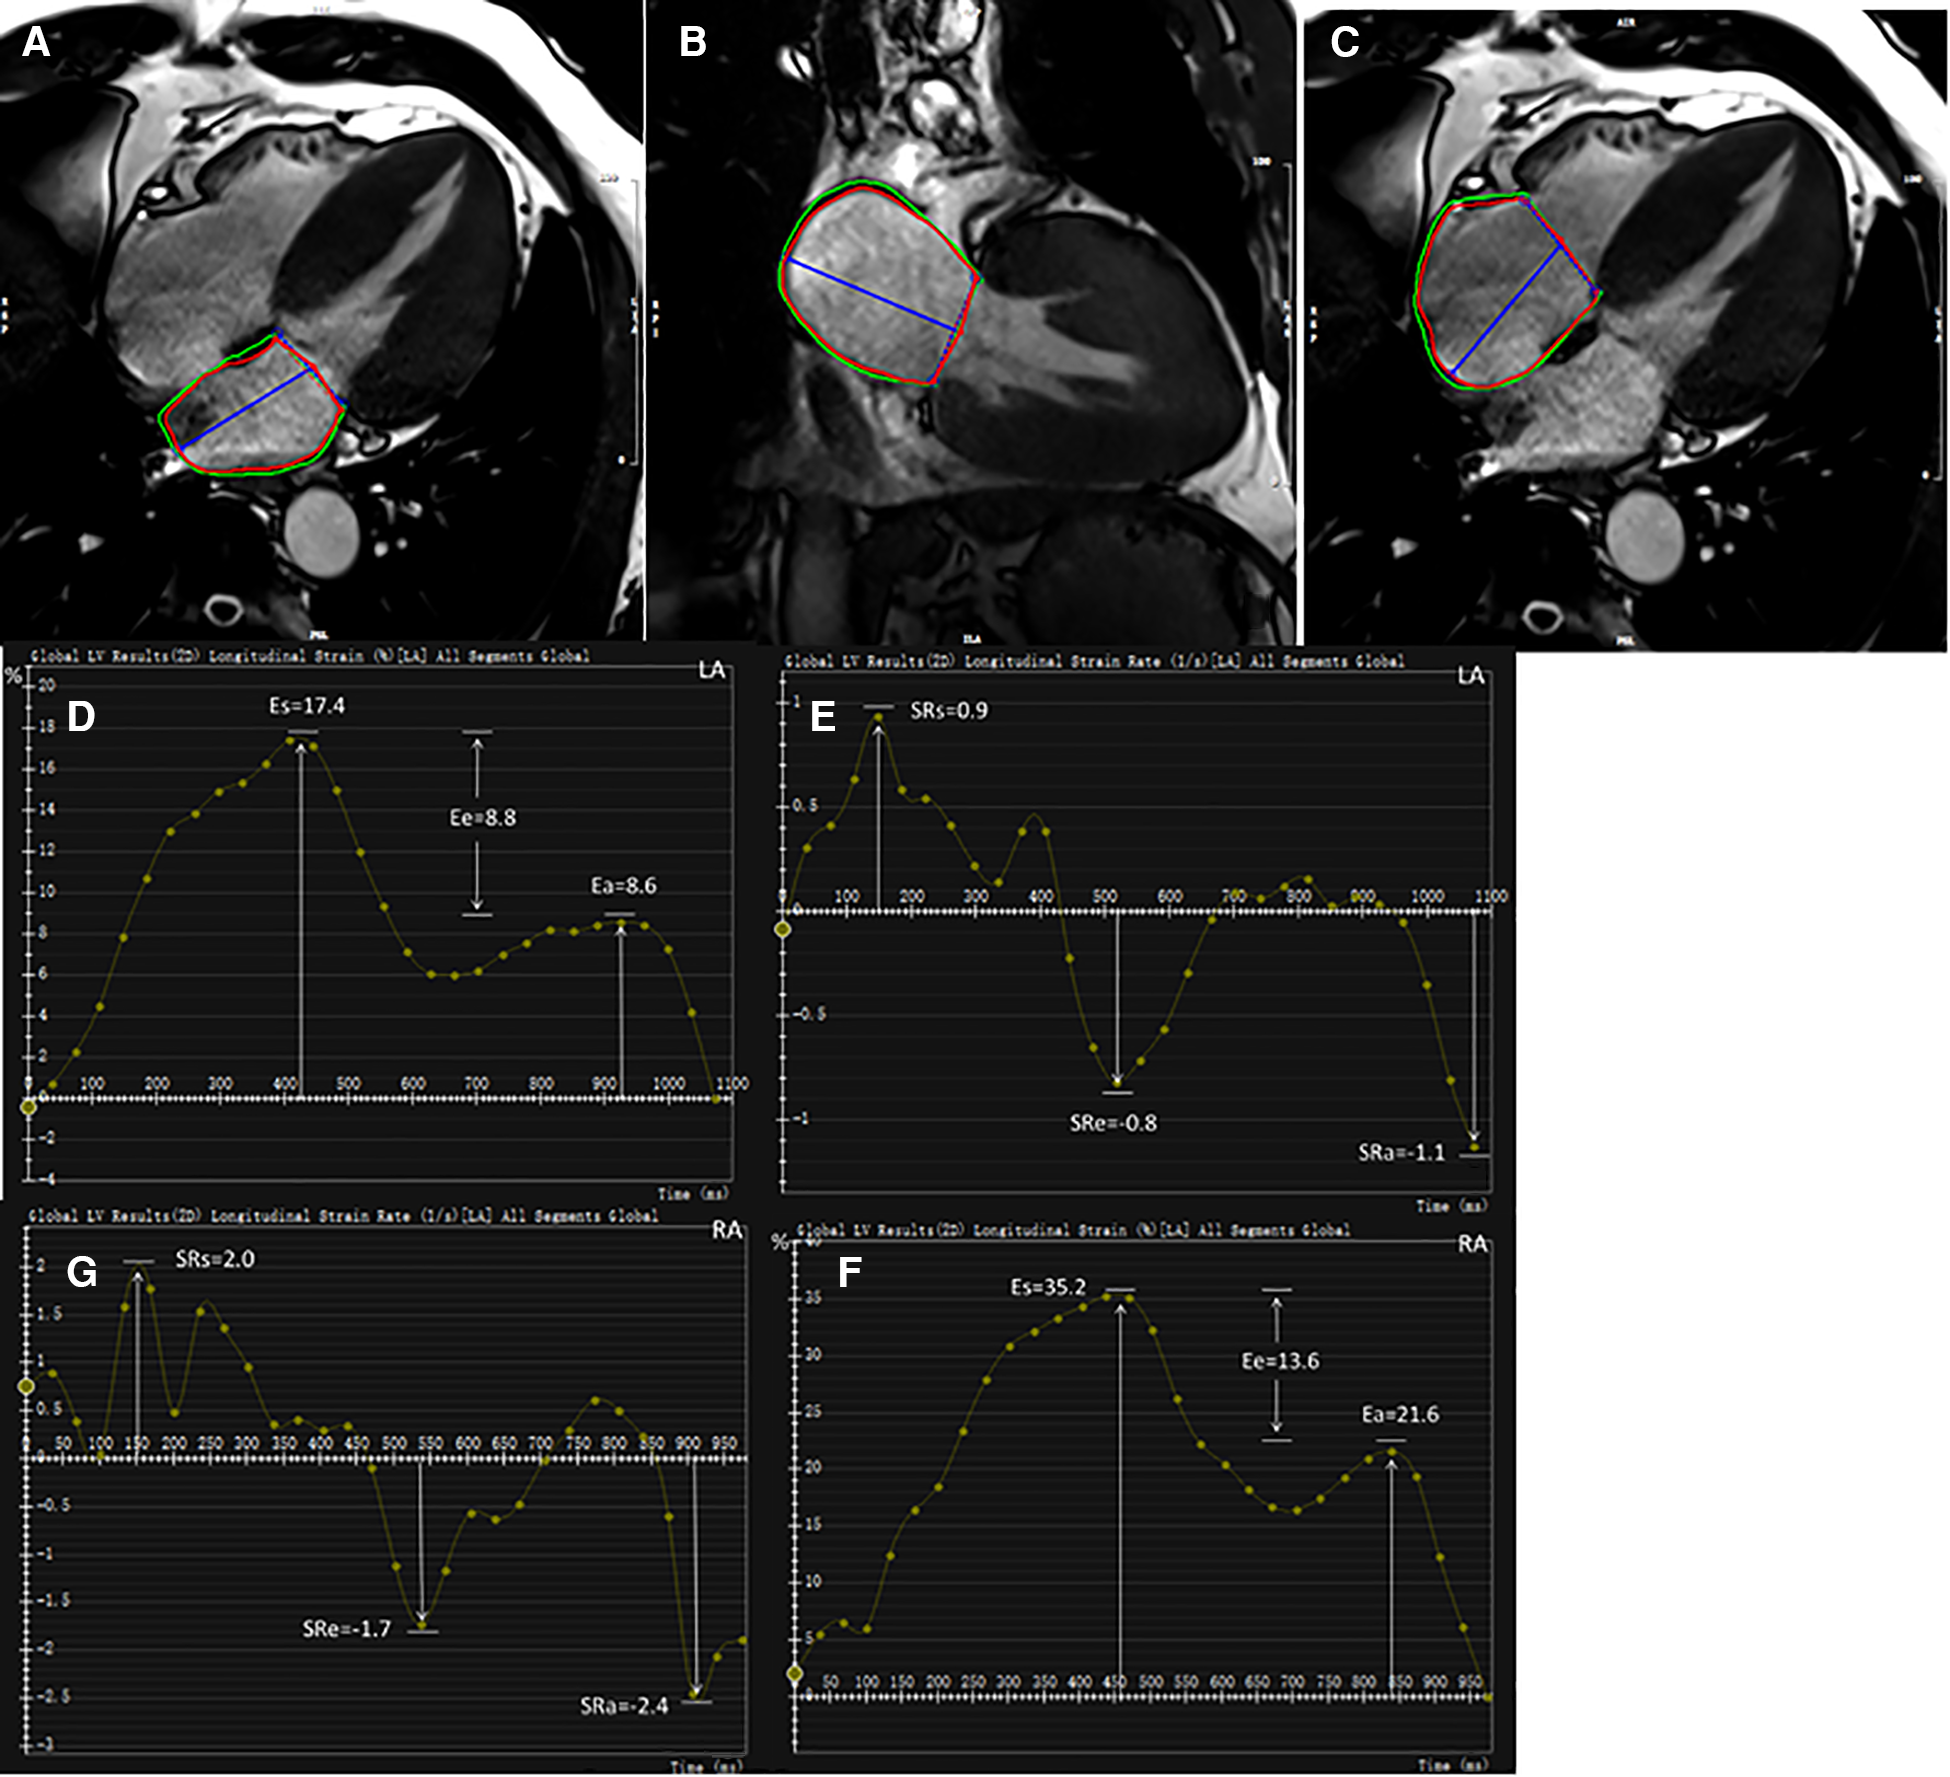

For strain analysis, LA endocardial and epicardial borders were tracked in two- and four-chamber views (Figures 1A,B). RA endocardial and epicardial borders were tracked in a four-chamber view (Figure 1C). The atrial borders were manually delineated in end-systole and end-diastole and then propagated to all frames automatically. Bi-atrial global longitudinal strain parameters were evaluated as ɛs (total strain, reflective of atrial reservoir function during ventricle systole), ɛe (passive strain, reflective of atrial conduit function during early ventricle diastole), and ɛa (active strain, reflective of atrial booster pump function during late ventricle diastole). Accordingly, their corresponding strain rate parameters were obtained as SRs (peak positive strain rate), SRe (peak early negative strain rate), and SRa (late peak negative strain rate). Five HCM and four HTN patients were excluded due to poor LA or RA tracking quality.

Figure 1

Representative HCM example for bi-atrial CMR feature tracking analysis. LA endocardial and epicardial contours at end-diastole shown on two- and four-chamber views (A,B). RA endocardial and epicardial borders at end-diastole shown on four-chamber view (C). Strain and strain rate parameters were obtained from strain curves (D,F) and strain rate curves (E,G), respectively. LA, left atrium; RA, right atrium; ɛs, total strain; ɛe, passive strain; ɛa, active strain; SRs, total strain rate; SRe, passive strain rate; SRa, active strain rate.